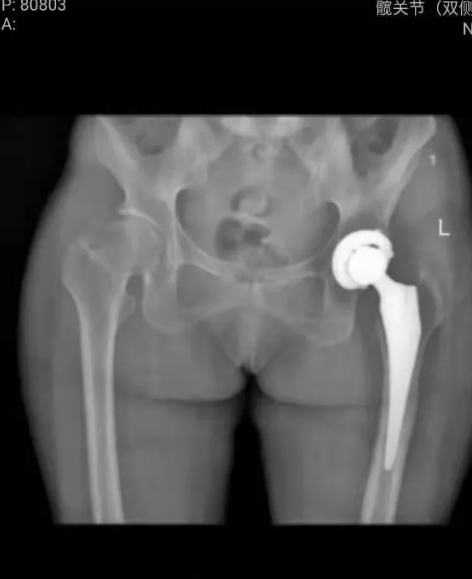

一位车祸致股骨颈骨折的大姨来到淄博市第四人民医院,骨二组副主任医师王宁接诊后,综合患者各项指标,与家属讨论决定行全髋关节置换术,术后第二天患者开始下地进行功能锻炼。